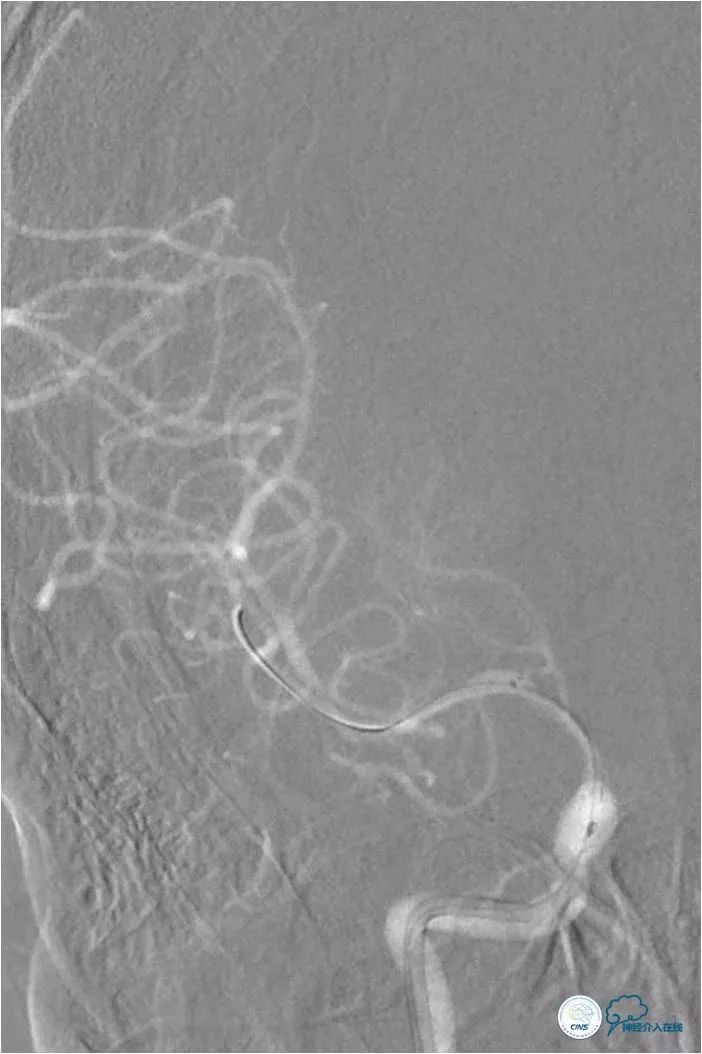

撤出球囊导管,后沿微导丝送入Wingspan自膨式支架(3.0mm×15mm),期间将导引导管送至右颈内动脉C3段,以增加系统支撑力(图8)。

图8

支架释放后造影提示支架贴壁良好,前向血流TICI 3级,脉络膜前动脉未受影响(图9)。

图9